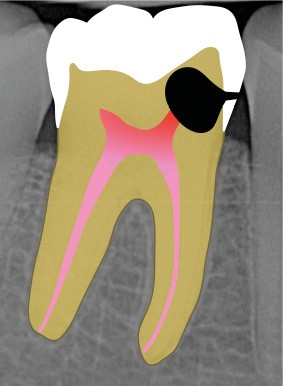

Perforation supra-osseuse (fig. 1)

Les perforations supra-crestales sont la plupart du temps iatrogéniques et surviennent lors de la réalisation de la cavité d’accès, ou de la recherche des entrées canalaires. Il s’agit généralement d’une communication avec un diamètre bien défini et aux contours nets. De ce fait, ce type de perforation est appelée « perforation à quatre parois ». Les perforations peuvent également être d’origine pathologique (résorption cervicale externe, carie active).